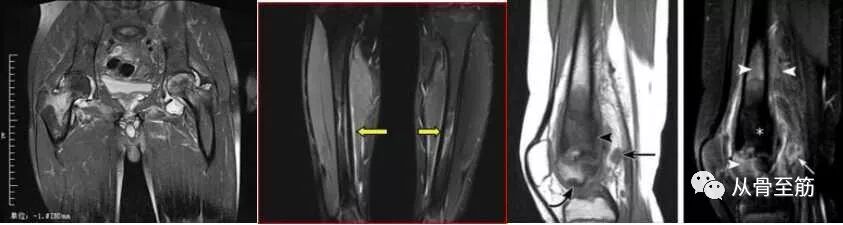

? ? 骨髓水肿这个名词,是随着磁共振成像(MRI)技术的应用而出现的,也就是说,只有在MRI检查中才能发现这种现象。病变区在MRI的T2WI压脂像上白,在T1WI上黑,与软组织水肿的影像学改变相似,故称为骨髓水肿。其他影像检查不能够发现或诊断骨髓水肿(包括X线片、CT、超声等)。“骨髓水肿”并不是独立的疾病,只是某些疾病中的表现之一或某一阶段。就像关节腔积液不是一个独立疾病一样。外伤造成的骨髓水肿通常称为骨挫伤或隐匿性骨折,这是由于骨小梁的微骨折,引起局部的出血水肿和局部微细结构的改变。

? ? 骨髓水肿可见于1、骨感染性疾病:如骨髓炎、结核;2、骨关节外伤:特别是X光片无明显骨折的挫伤;3、肿瘤,转移性病变更明显;4、骨的缺血性疾病:如股骨头坏死、距骨坏死;5、骨关节免疫性疾病:最常见的是类风湿性关节炎、强直性脊柱炎等;5、退行性骨关节病;血液系统的疾病:白血病,骨髓瘤等;7、其他:中毒性骨病,如镉中毒等造成骨溶解而伴骨髓水肿;痛风性关节病等。